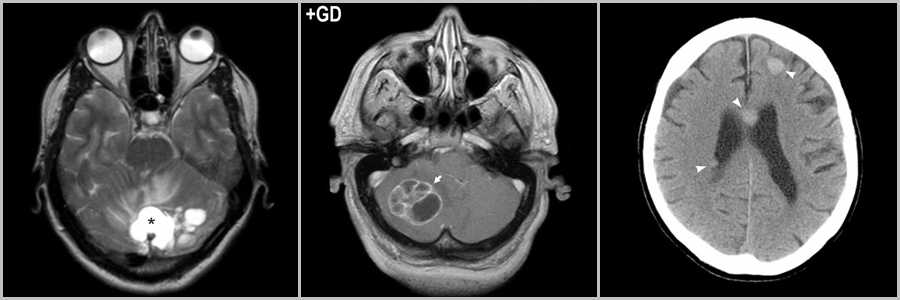

Гемангиобластома

Гемангиобластома — кистозная опухоль с мелким пристеночным узлом, располагается инфратенториально, может встречаться интрамедуллярно в спинном мозге, ассоциирована с болезнью фон Гиппеля-Линдау, при которой обнаруживается поражение других органов и систем, в частности почек (поликистоз) и надпочечников (феохромоцитома). При перфузионном исследовании отмечается выраженное превалирование показателей гемодинамики (rCBF и rCBV) у гемангиобластомы над пилоцитарной астроцитомой . Кроме того, астроцитома встречается чаще у детей и подростков, а гемангиобластома — у взрослых.

Рис.10 * Рис. 10 был заимствован из “Диагностическая нейрорадиология” 2009г. Корниенко В.Н., Пронин И.Н. 2009г. с целью наглядной демонстрации патологического процесса.

Мелкая гемангиобластома в области левой мозжечковой миндалины (стрелка на рис.10). После внутривенного контрастирования происходит интенсивное накопление контраста в пристеночном сосочке (стрелка на рис.10). Объёмный мозговой кровоток гемангиобластомы (стрелка на рис.10) существенно превышает те же показатели пилоцитарной астроцитомы (головка стрелки на рис.10).